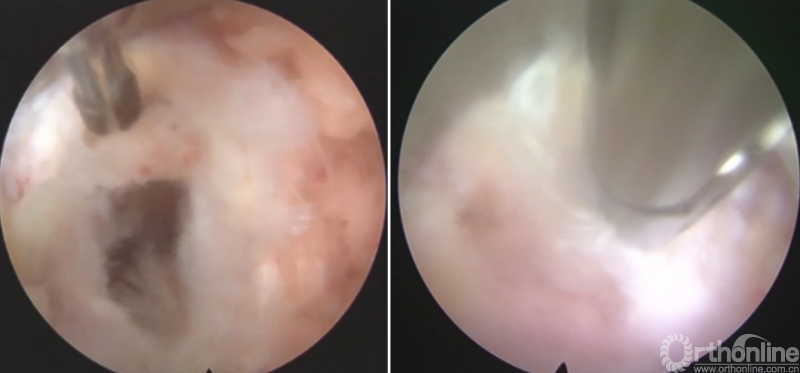

第六步“切”:切除椎间盘;

第七步“旋”:旋转舌形套管保护神经根;

第八步“铰”:盲视下可撑开铰刀置入,撑开并处理上下终板;

第九步“填”;椎间隙填塞植骨;

第十步“置”:置入融合器、经皮钉。